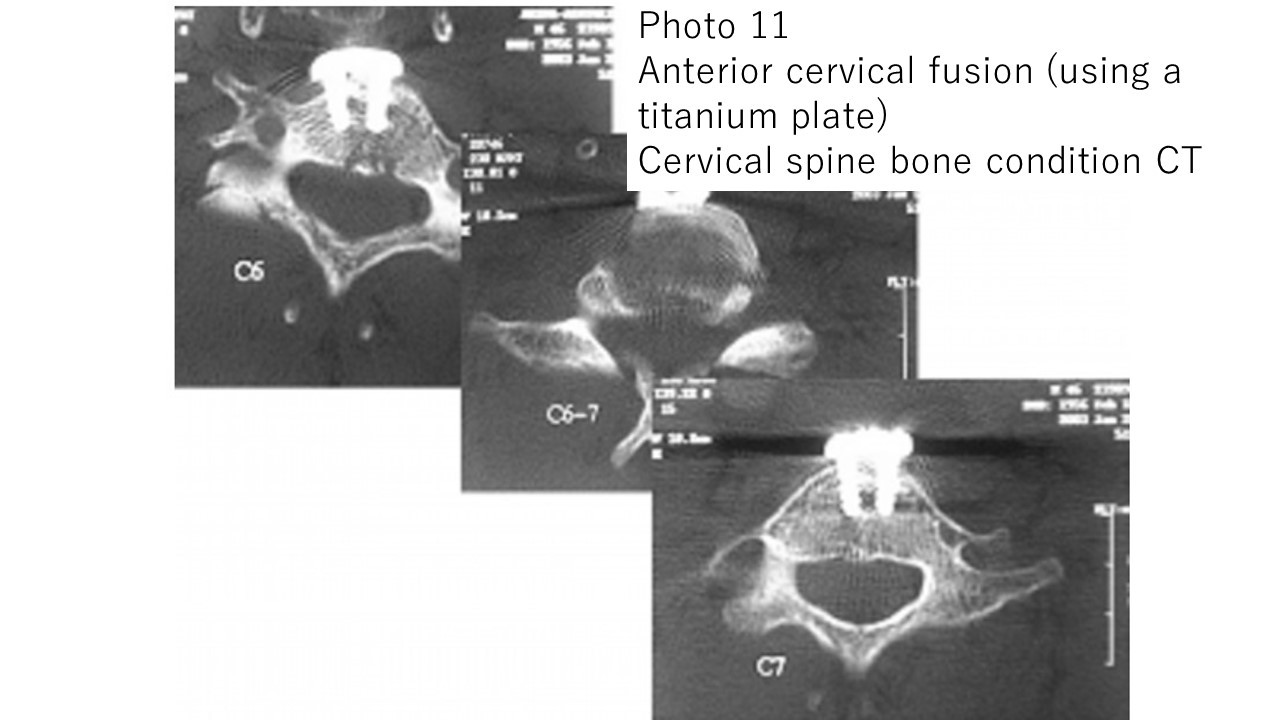

Photo 11: Anterior fusion surgery (using a titanium plate) was performed for a cervical fracture (traffic accident).

Postoperative CT scan of the cervical spine. The titanium plate is firmly fixed with four screws.

The patient was discharged home on foot 2 weeks after surgery.